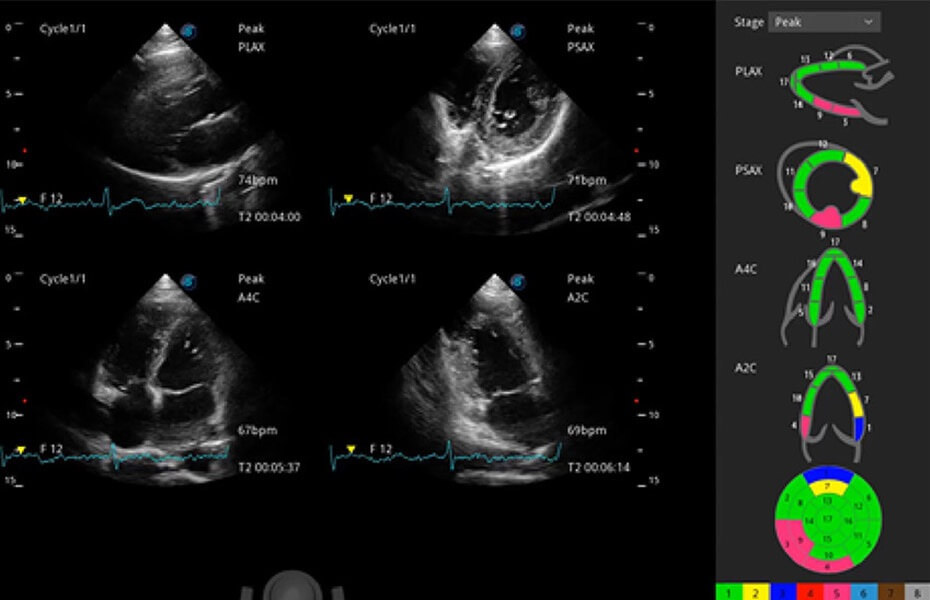

ProPet 60 作為一款高端臺(tái)式動(dòng)物超聲設(shè)備,為動(dòng)物醫(yī)生的日常診斷提供了一系列貼合動(dòng)物臨床需求、解決臨床實(shí)際問(wèn)題的高級(jí)成像功能。憑借全系列高清探頭,滿(mǎn)足醫(yī)生對(duì)腹部、心臟、生殖、淺表、肌骨等成像的所有需求,切實(shí)幫助您提升檢查效率,提高診斷信心。